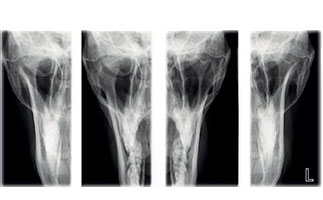

臨床2D画像

3ジョイント(SCARA3)プランメカ ProMax 2D S3イメージングデバイスは、パノラマ、顎外咬翼、TMJそして上顎洞などに対応するよう設計されています。

2ジョイント(SCARA2)プランメカ ProMax 2D S2 は、パノラマ、顎外咬翼、TMJ、および上顎洞撮影のための基本プログラムが含まれています。